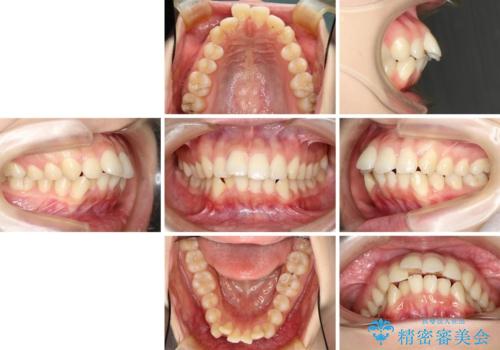

- 口元の突出感を気にして来院された患者様です。

上下左右の第一小臼歯4本を抜歯して口元を下げる治療計画としました。

目立たない装置が希望であったため、上顎が裏側装置である、ハーフリンガル装置を選択されました。

3年半ほどで終わる予定でしたが、途中引っ越し、出産、引っ越し、出産を繰り返し、なかなか来院することができず、装置を外すまでに8年以上の期間がかかってしまいました。